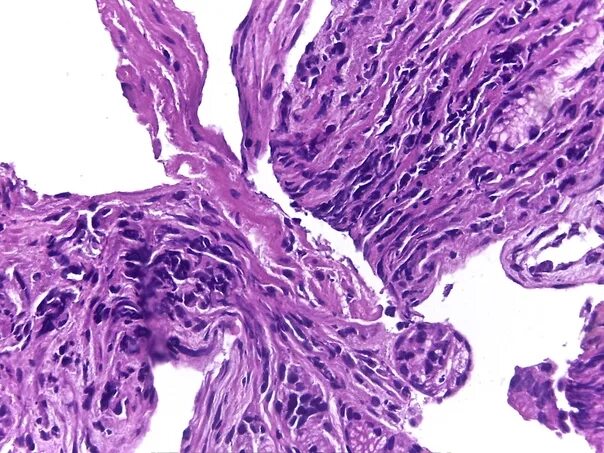

Гистологическая вырезка